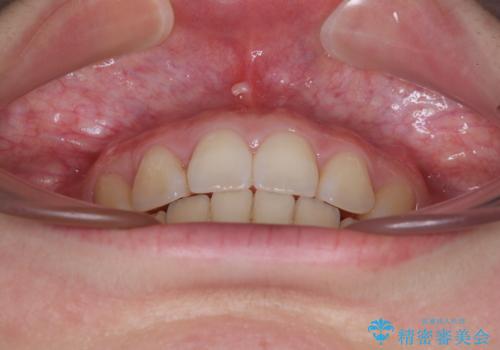

飛び出した上顎前歯 抜歯矯正でスッキリとした横顔に

順調に治療が進み、2年弱で想定していたとおりの仕上がりにて治療を終えることができました。